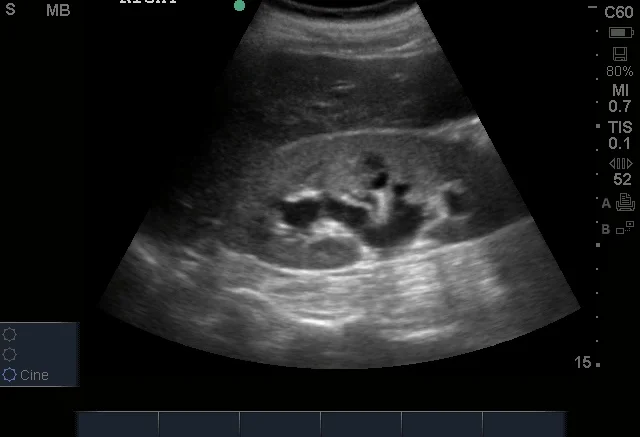

![]()

Hydronéphrose sévère. © POCUS Atlas

➡️ Plus l’hydronéphrose est marquée, plus l’obstruction est significative ou prolongée.